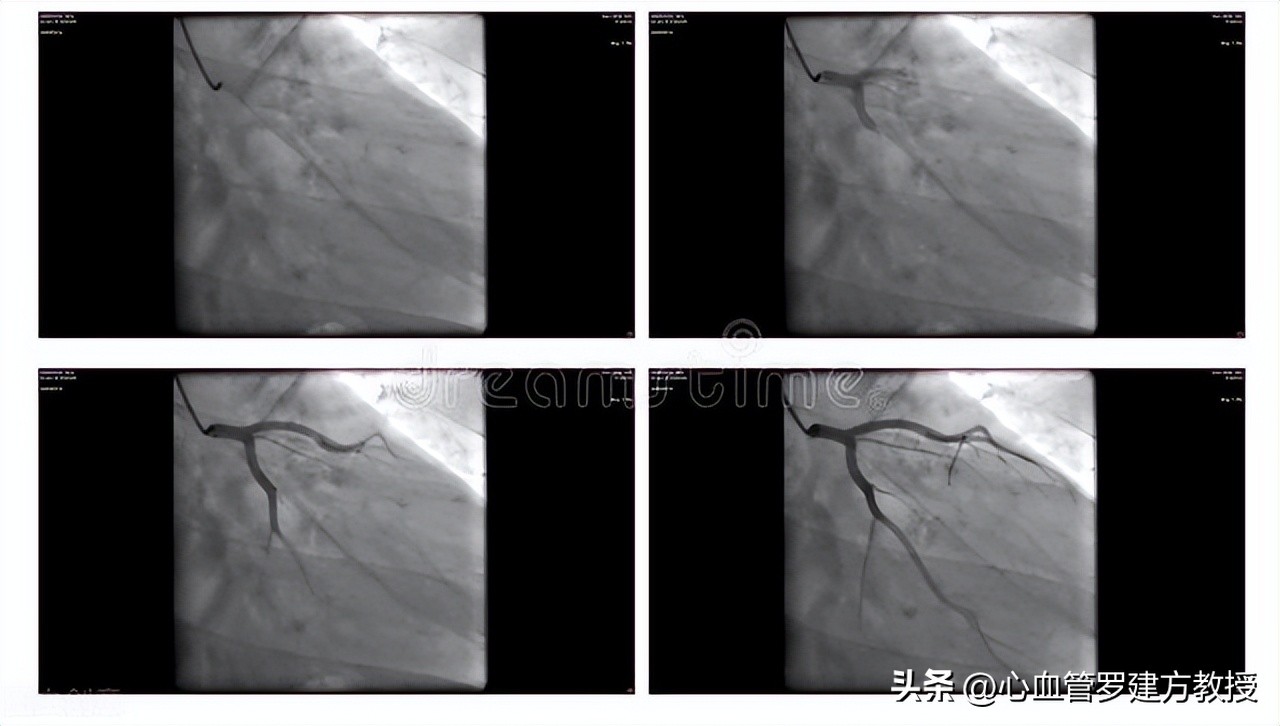

冠脉造影需要从外周大动脉进导管,一般来说,会选择股动脉或者是桡动脉来插入导管直至主动脉根部,再选择性地将导管送入左冠或者右冠状动脉开口,注射入造影剂,再通过X线透视下来显示整个冠脉的形态特点。通过冠脉造影术可以直接看到心脏血管里面有没有病变,是否存在有堵塞的情况,具体的病变堵塞的严重程度怎样,冠脉造影是目前诊断冠心病最直接也最可靠的方法,它能非常清楚的显示冠脉有无狭窄,其狭窄的部位、狭窄程度、范围以及病变处血管的血流情况等等,医生可以根据冠脉造影的结果,再进一步的指导后续的治疗措施和方案。冠脉造影是国内外公认的诊断冠心病的“金标准”。